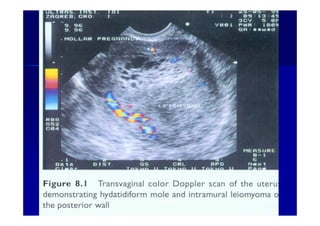

Color Dopplor facilitates visualization of the enlarged spiral

arteriesclose proximity to the “ snow storm” appearance

Color Doppler image of a hydatidiform mole and surrounding

vessels. The uterine artery is easily identified from its anatomical

location.1919--SepSep--1212 o wardao warda